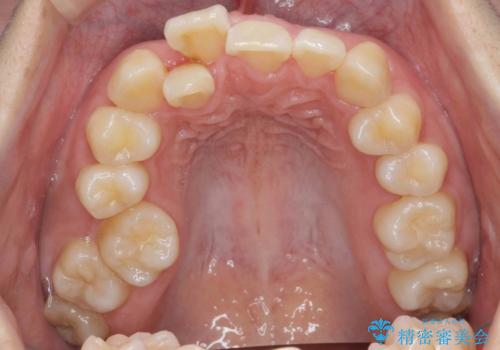

また、上の前歯を下げるために抜歯という選択肢もありましたが、前歯の大きさを若干小さく削り、奥歯を後ろに下げるというのを試みて、難しいようなら抜歯という形で進めました。

結果、遠心移動もスムーズに進み大きく前歯を下げることができました。

前歯の角度もよくなり、奥歯のかみ合わせも問題なく、上は非抜歯で口元も閉じやすくなりました。